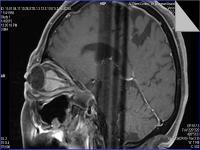

Medical imaging is an important investigative tool will help doctors to reach for the diagnosis of certain diseases, and the the advanced and high-quality imaging technologies are an important factor in maintaining the health of patients and accurate diagnosis of pathological lesions.